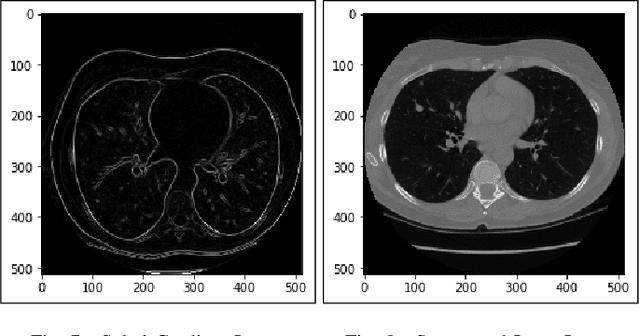

Lung cancer is one of the death threatening diseases among human beings. Early and accurate detection of lung cancer can increase the survival rate from lung cancer. Computed Tomography (CT) images are commonly used for detecting the lung cancer.Using a data set of thousands of high-resolution lung scans collected from Kaggle competition [1], we will develop algorithms that accurately determine in the lungs are cancerous or not. The proposed system promises better result than the existing systems, which would be beneficial for the radiologist for the accurate and early detection of cancer. The method has been tested on 198 slices of CT images of various stages of cancer obtained from Kaggle dataset[1] and is found satisfactory results. The accuracy of the proposed method in this dataset is 72.2%